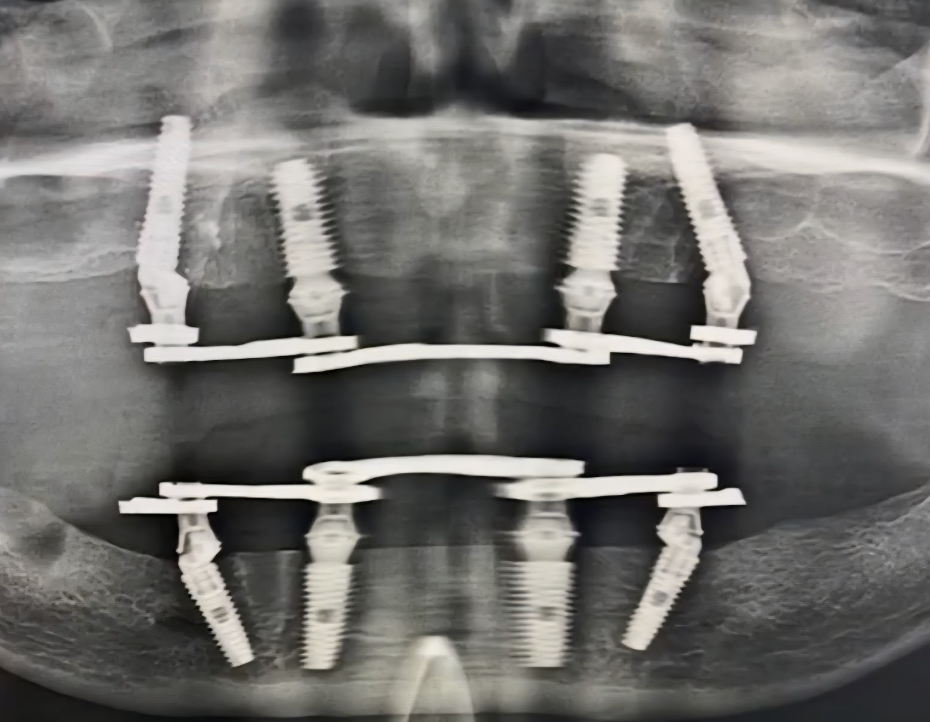

Стоматологи назначили имплантацию по протоколу «Всё‐на-4». Это когда в каждую челюсть вживляется по 4 импланта, и на них держится постоянный акриловый протез.

«Всё-на-4» — самый бюджетный вариант. Есть более дорогая операция, на 6 или 8 имплантах. Но мне, пожилому человеку со слабой костной тканью, достаточно и четырёх имплантов.